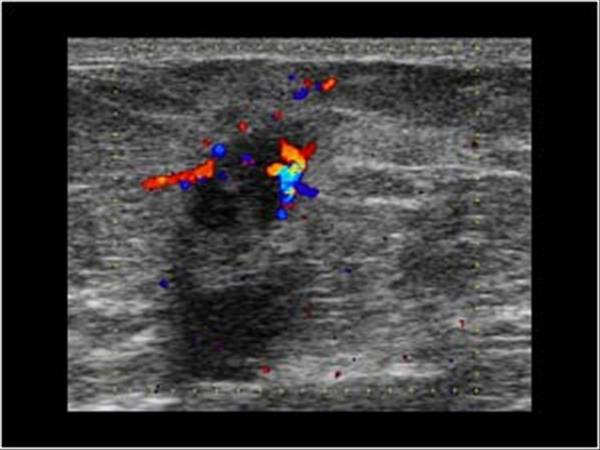

Ung thư vú

Ung thư vú - Ảnh 4

» Thông tin: Nữ giới – 59 tuổi.

» Lâm sàng: Khối tuyến vú.